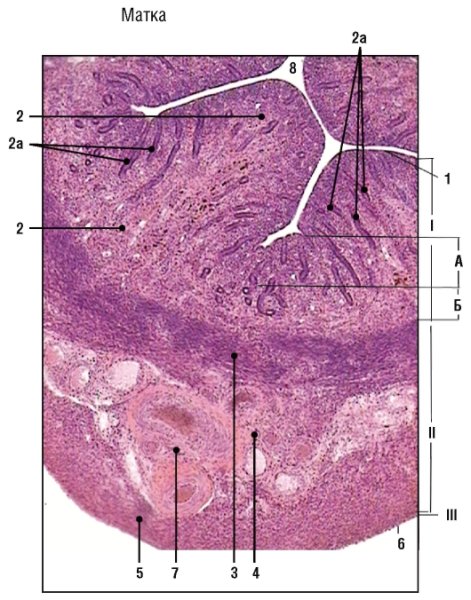

В гистологии матки, также известной как эндометрий, можно наблюдать различные ткани и структуры. На рисунке представлена детальная схема анатомии матки, которая помогает увидеть основные элементы ее строения. Например, это включает в себя миометрий, состоящий из гладкой мышечной ткани, который окружает полость матки, и эндометрий, слой клеток, который выстилает внутреннюю сторону матки. Рисунок также может показывать железистые структуры, которые присутствуют в эндометрии, и кровеносные сосуды, обеспечивающие питание тканей матки. Все эти детали помогают лучше понять анатомию и функции матки, что важно при изучении различных состояний и заболеваний этого органа.

Строение матки гистология рисунок